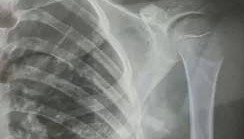

10月23日,内蒙古赤峰市宁城县苏木皋小学一学生被老师打伤致锁骨骨折。10月31日,家长贾女士给生...